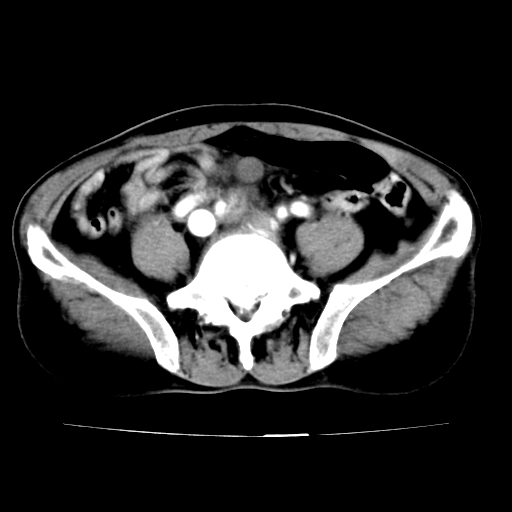

男,75岁,腹痛月余,彩超发现脐周腹主动脉异常回声。临床诊断:腹主动脉瘤。

ct诊断:右骼总动脉囊性动脉瘤并瘤内附壁血栓形成,与下腔静脉之间形成动静脉瘘。

请问各位老师:能排除动脉瘤破裂的可能吗?

各位老师注意到下腔静脉的充盈缺损了吗?注意到动静脉漏了吗?

当时是扫描的标准动脉期,可是下腔静脉与腹主动脉同步强化且幅度一致。所以我想动静脉瘘是存在的。